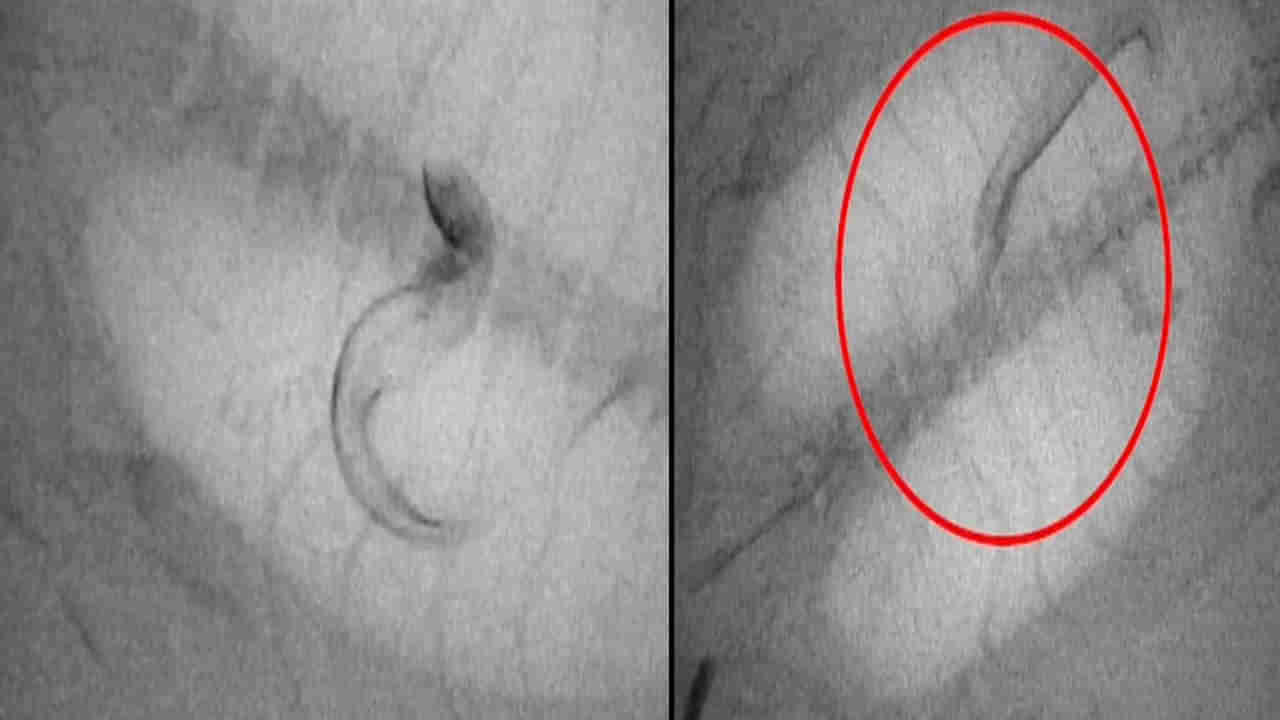

కొన్ని జంతువులకు పదునైన ముళ్లు లేదా తమను తాము రక్షించుకునేందుకు తమ శరీరంలోనే కొన్ని నిష్క్రియాత్మక రక్షణలు ఉంటాయని పరిశోధకులకు అంటున్నారు. అవే వాటికి వేటాడిన జంతువుల నుంచి బయటపడేందుకు సాయపడతాయట. పరిశోధకులు సుమారు 32 జువెనైల్ ఈల్స్కు ఎక్స్-రే వీడియో సిస్టమ్కు కనిపించేలా చేసే కాంట్రాస్ట్ ఏజెంట్ను ఇంజెక్ట్ చేశారు. తర్వాత వాటిని చిన్న ట్యాంకులలోని డార్క్ స్లీపర్( ఓడోంటోబుటిస్ అబ్స్క్యూరా) అనే పిలిచే చేపలోకి పంపారు.

ఆ చేప ఈల్స్ను తిన్న వెంటనే.. సదరు ఈల్స్ చేప కడుపు నుంచి తప్పించుకోవడానికి తీవ్రంగా ప్రయత్నించాయి. చివరికి కేవలం తొమ్మిది మాత్రమే ప్రాణాలతో బయటపడ్డాయని పరిశోధకులు పేర్కొన్నారు. కొన్ని కడుపులో తిరుగుతూ, బయటపడే మార్గాన్ని వెతకగా.. మరికొన్ని విజయవంతంగా తప్పించుకున్నాయని తెలిపారు.